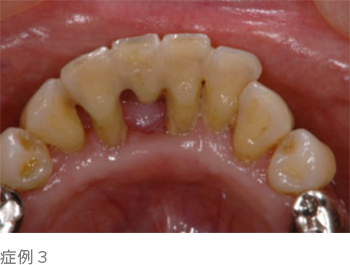

上の写真のように歯と歯の隙間が広くなったり、歯があらぬ方向に動き出し、出っ歯になったりもします。

歯を失うという事は、歯の周りの骨が大きく喪失し、顔の表情にも大きな変化をもたらします(写真下)。